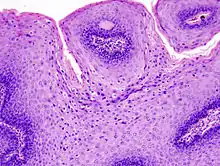

Micrograph of a genital wart with the characteristic changes (parakeratosis, koilocytes, papillomatosis). H&E stain.

The diagnosis of genital warts is most often made visually, but may require confirmation by biopsy in some cases.[20] Smaller warts may occasionally be confused with molluscum contagiosum.[19] Genital warts, histopathologically, characteristically rise above the skin surface due to enlargement of the dermal papillae, have parakeratosis and the characteristic nuclear changes typical of HPV infections (nuclear enlargement with perinuclear clearing). DNA tests are available for diagnosis of high-risk HPV infections. Because genital warts are caused by low-risk HPV types, DNA tests cannot be used for diagnosis of genital warts or other low-risk HPV infections.[4]